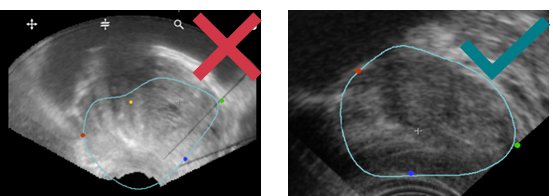

During the MRI/US fusion, on the axial and sagittal views, US and MRI prostate contours are not continuous and don't seem to be the same prostate image.

- Make sure the blue contour fits correctly with the prostate shape on MRI & US: